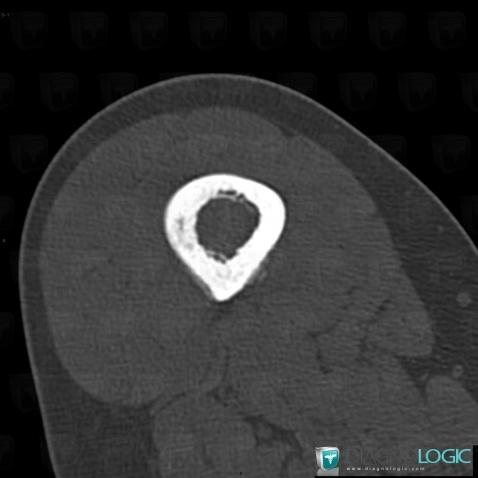

Ewing sarcoma, Femur - Mid part, CT

Here is the specific information in the key image above:

- Diagnosis Ewing sarcoma, Location(s) Femur - Mid part, with gamuts Localised periosteal reaction, Asymmetric periosteal reaction